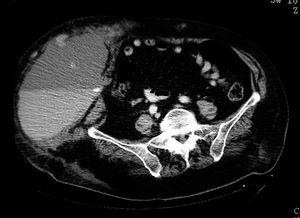

Casos en imagen 2

Miguel A Pastrama, Patricia Fraga, Miguel A Cavero, Roberto Peraira

Radiologia 2005;47:340